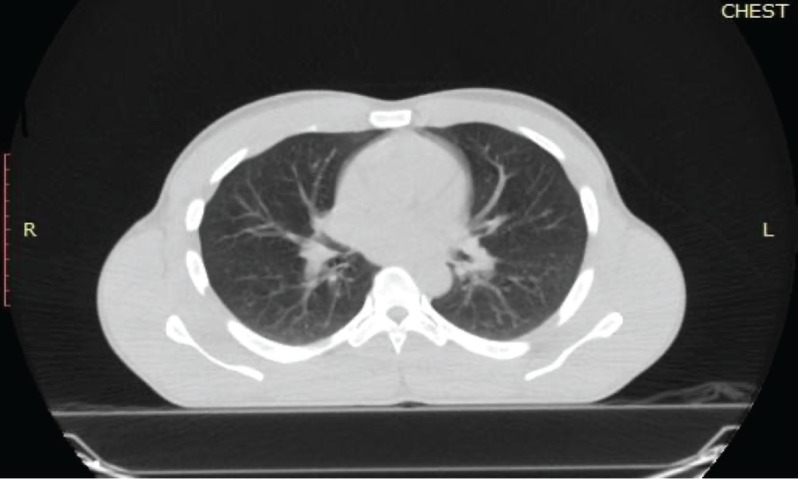

Dermatofibrosarcoma protuberans (DFSPs) is a low-grade mesenchymal tumour of dermal origin. Although lung metastasis is common, primary breast involvement is a very rare occurrence. The head and neck region, trunk and extremities are the common primary sites even though any site of the body may be potentially involved. Complete surgical resection with negative margins is the standard of care for nonmetastatic cases of DFSP. To the best of our knowledge, there have been no previous reports of metastatic DFSP of the breast to the lungs among male patients in sub-Saharan Africa. This case report presents data on a 32-year-old male with metastatic DFSP of the left breast to the lungs who was successfully treated with 800 mg daily imatinib mesylate therapy and achieved a complete radiological and clinical response after 1 year of palliative therapy.